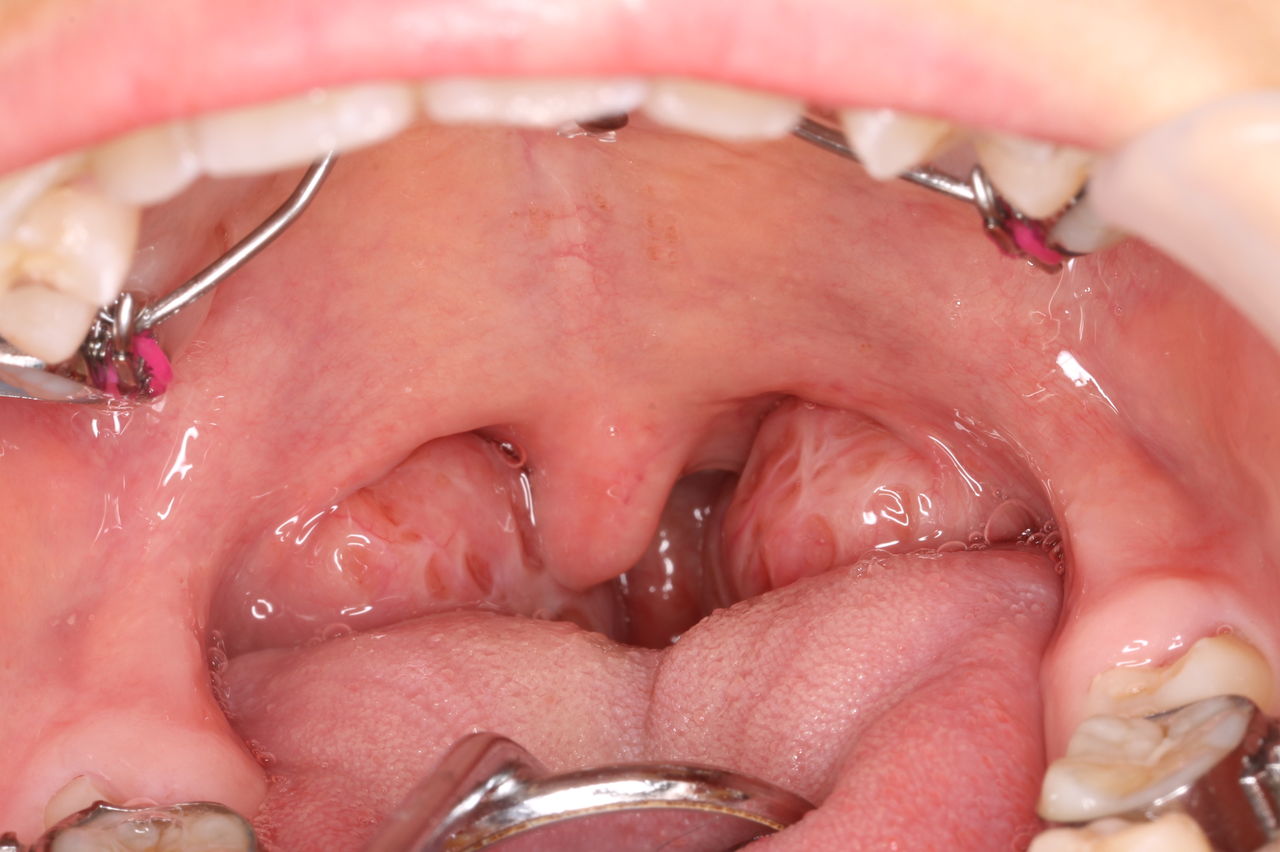

扁桃摘出術の適応判断の一助に-咽頭/口蓋扁桃の気道占有率を年齢別に定量化